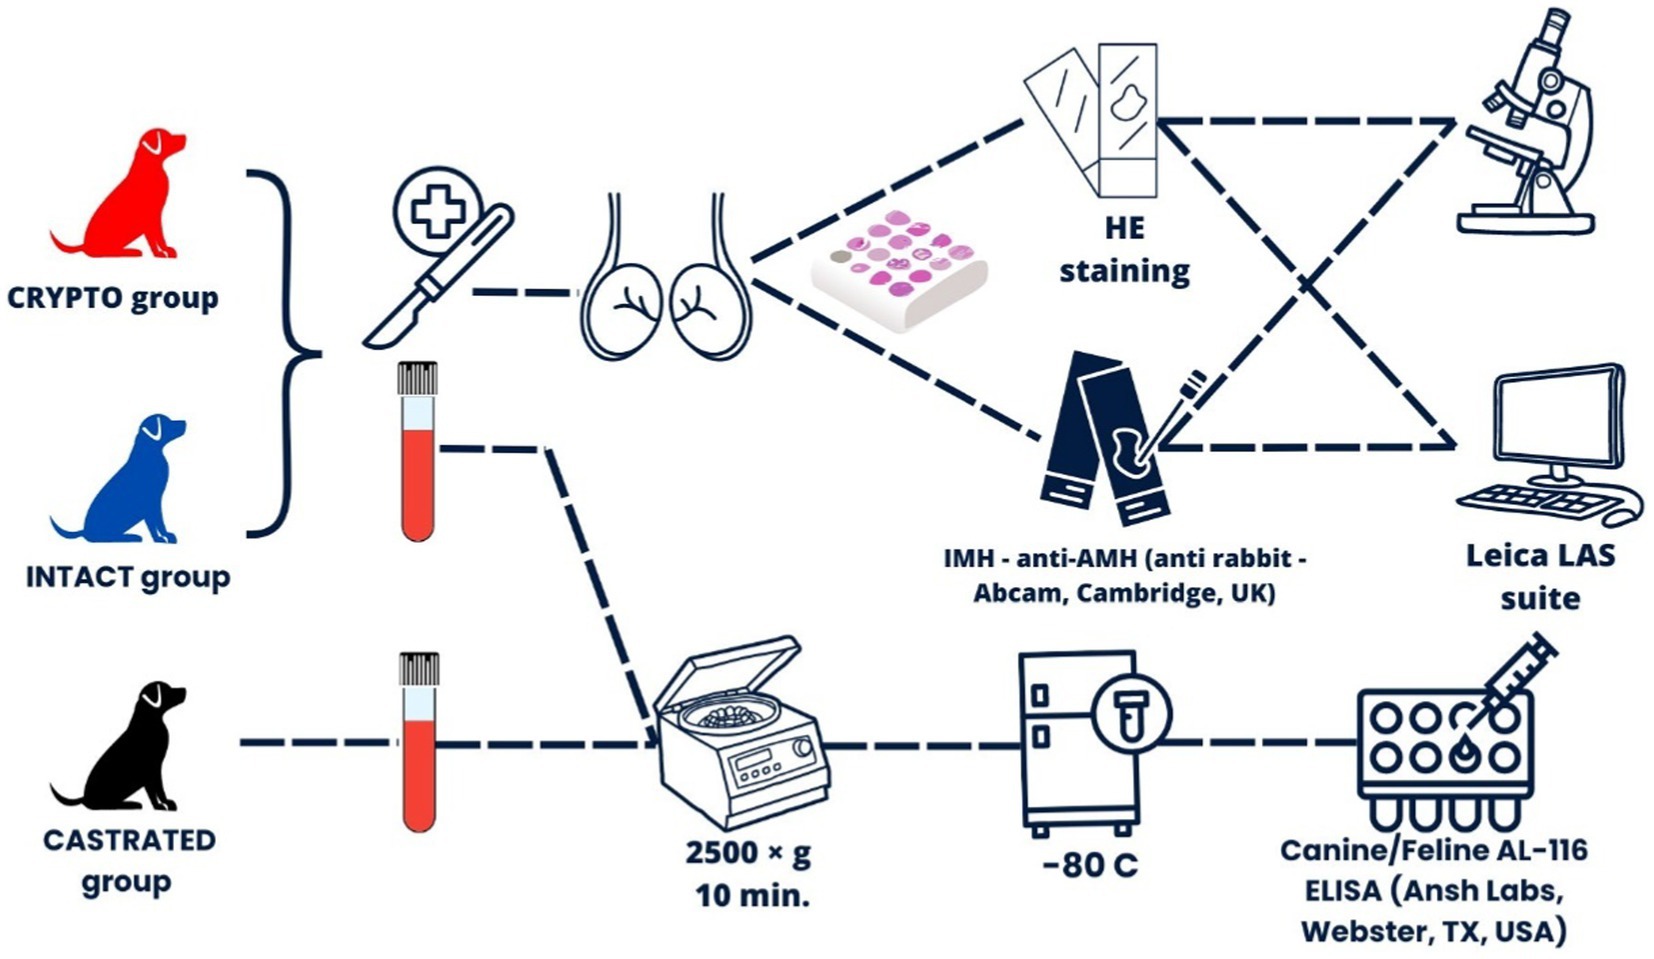

Métodos: Se investigó la relación entre los niveles séricos de AMH y la expresión tisular de AMH con la alteración de la espermatogénesis y la alteración de la histología. Se determinaron los niveles séricos de AMH en individuos intactos, criptorquídicos y castrados utilizando un kit de ELISA inmunoenzimático y se compararon entre subgrupos en función de la ubicación testicular. La inmunoexpresión tisular de AMH se cuantificó diferencialmente en dos regiones de interés (ROIs), el espacio intersticial y el túbulo seminífero, tanto en gónadas descendidas como retenidas. Además, los testículos se analizaron mediante análisis histomorfométrico en túbulos seminíferos, mientras que la espermatogénesis se evaluó mediante la puntuación de Johnsen.

Se recogieron muestras de sangre de todos los perros que participaron en el estudio serológico. Las muestras se extrajeron de la vena cefálica y se almacenaron en tubos de recolección lisos de tapa roja sin aditivos (BD Vacutainer, Plymouth, Reino Unido). En el caso de los perros CRYPTO e INTACT, se tomaron muestras antes de someterse a la orquiectomía, y en el caso de los perros del grupo CASTRADO, las muestras se recogieron al menos 6 meses después de la castración. Después de dejar que la sangre coagulara durante 5 minutos a temperatura ambiente, las muestras se centrifugaron a 2.500×g durante 10 minutos. A continuación, el suero resultante se almacenó a -80 °C hasta su posterior procesamiento.

2.2 Evaluación de los niveles séricos de AMH

Los niveles séricos de AMH se cuantificaron utilizando un kit de inmunoensayo validado de tres pasos tipo sándwich (Canine/Feline AL-116 ELISA, Ansh Labs, Webster, TX, USA), que se ha utilizado previamente en estudios con perros (25, 26). Cada pocillo recubierto de la microplaca se trató inicialmente con 75 μL de tampón de ensayo AMH canino, de acuerdo con las recomendaciones del fabricante. Posteriormente, después de añadir un volumen de 25 μL de calibradores, controles y muestras de suero, la placa se sometió a una incubación de 60 minutos a temperatura ambiente en un agitador de microplacas orbitales a 600 rpm. Después de la incubación, los pocillos se lavaron a fondo y se añadieron 100 μL de conjugado anticuerpo-biotina a cada pocillo, seguido de otra incubación en las mismas condiciones según el protocolo del fabricante. Después de pasos de lavado adicionales, los pocillos se trataron con la enzima conjugada Estreptavidina-HRP durante 30 min. La reacción se desarrolló con una incubación de 10 minutos utilizando 100 μL de solución de cromógeno TMB y se detuvo con 100 μL de solución de parada. La absorbancia de la placa se leyó a 450 nm, con corrección de la longitud de onda de fondo a 630 nm, utilizando un lector de microplacas de absorbancia PR 4100 (Bio-Rad Laboratories, Hercules, CA, USA). El coeficiente de variación intraensayo fue inferior al 10%. Dado que todas las muestras se procesaron simultáneamente en un solo lote, no se calculó ningún coeficiente de variación entre ensayos. El límite de detección del kit fue de 0,015 ng/mL.

2.3 Preparación de muestras de tejido

Los bloques de parafina previamente almacenados se seccionaron repetidamente a 4 μm para crear dos lotes diferentes. El primero se tiñó con hematoxilina y eosina (HE) y se dirigió a evaluación microscópica convencional, seguido de análisis histomorfométrico y evaluación de espermatogénesis. El segundo lote se reservó para la evaluación inmunohistoquímica.

2.3.1 Tinción inmunohistoquímica

Las secciones de tejido dedicadas se montaron en portaobjetos recubiertos de 3-aminopropiltrietoxisilano. Estos portaobjetos se sometieron a desparafinación con xileno, seguida de rehidratación en concentraciones decrecientes de etanol (100, 96, 50%) y 100% deH2O. Para la recuperación de antígenos, los portaobjetos se colocaron en una caja llena de agua destilada y tampón de citrato (pH 6.0), que luego se colocó dentro de una olla a presión que contenía 600 mL de agua destilada. El sistema (cocina + correderas) se calentó en el microondas a 850 W durante 12 min y luego a 300 W durante 10 min. Después de la recuperación, la caja que contenía los portaobjetos se enfrió a temperatura ambiente durante 20 minutos.

Después de un lavado de 5 minutos con PBS, se añadieron 200 μL de H2O2 a cada sección durante 5 min. A continuación, los portaobjetos se lavaron dos veces con PBS. El anticuerpo primario utilizado fue anti-AMH C-terminal (anti-conejo, Abcam, Cambridge, Reino Unido) en una dilución de 1:400 (diluyente de anticuerpos con reducción de fondo, DAKO Agilent – S3022832, Santa Clara, CA, EE. UU.). Los portaobjetos se incubaron con el anticuerpo primario diluido durante 30 minutos, se lavaron dos veces con PBS y luego se expusieron a 200 μL/portaobjetos de conejo Envision Link (DAKO Agilent – K400311-2) durante 30 minutos.

Después de esta incubación, los portaobjetos se lavaron dos veces en PBS durante 5 min y luego se trataron con 200 μL/portaobjetos de solución de 3,3-diaminobenzidina (DAB, DAKO Agilent – K346811-2) para una incubación final de 30 min. Finalmente, los portaobjetos se lavaron nuevamente en PBS durante 5 minutos, se contratiñeron con hematoxilina, se deshidrataron, se montaron con cubreobjetos y se almacenaron para su posterior análisis.

2.4 Análisis de muestras de tejido

Los portaobjetos fueron evaluados de forma ciega, por un operario capacitado, utilizando un microscopio Leica DM5500 B (Leica Microsystems CMS GmbH, Wetzlar, Alemania). La adquisición adicional de imágenes, el procesamiento digital y el análisis de píxeles se realizaron utilizando Leica Application Suite (LAS versión 4.13, Wetzlar, Alemania).

El diseño experimental se ilustra en la Figura 1.